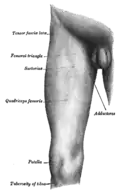

Front and medial aspect of right thigh.

Front and medial aspect of right thigh.

The tuberosity of the tibia gives attachment to the patellar ligament, which attaches to the patella from where the suprapatellar ligament forms the distal tendon of the quadriceps femoris muscles. The quadriceps muscles consist of the rectus femoris, vastus lateralis, vastus medialis, and vastus intermedius. These quadriceps muscles are innervated by the femoral nerve.[1] The tibial tuberosity thus forms the terminal part of the large structure that acts as a lever to extend the knee-joint and prevents the knee from collapsing when the foot strikes the ground.[1] The two ligaments, the patella, and the tibial tuberosity are all superficial, easily palpable structures.[2]